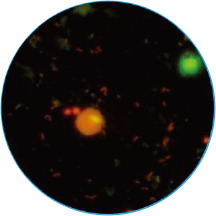

免疫荧光法结果展示及判读示例

阴道分泌物多重免疫荧光染色技术,具备形态学与荧光学的双重优势。可以同时对上皮细胞,白细胞,乳酸杆菌,线索细胞,念珠菌和毛滴虫等进行染色区分,既能检测阴道相关病原体感染,也能评估其阴道微生态和阴道清洁度等是否正常,为临床的快速诊断和治疗提供帮助。

毛滴虫

橙黄色荧光

梨形或椭圆形,直径

10~13 μm稍大于白细胞